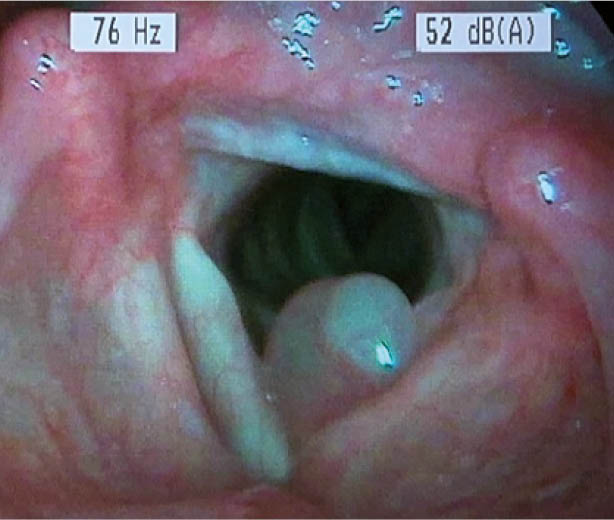

Stimmlippenpolyp (Abb. 3):

Es spielen ursächlich mechanische Faktoren wie Stimmüberlastung und Rauchen eine Rolle.